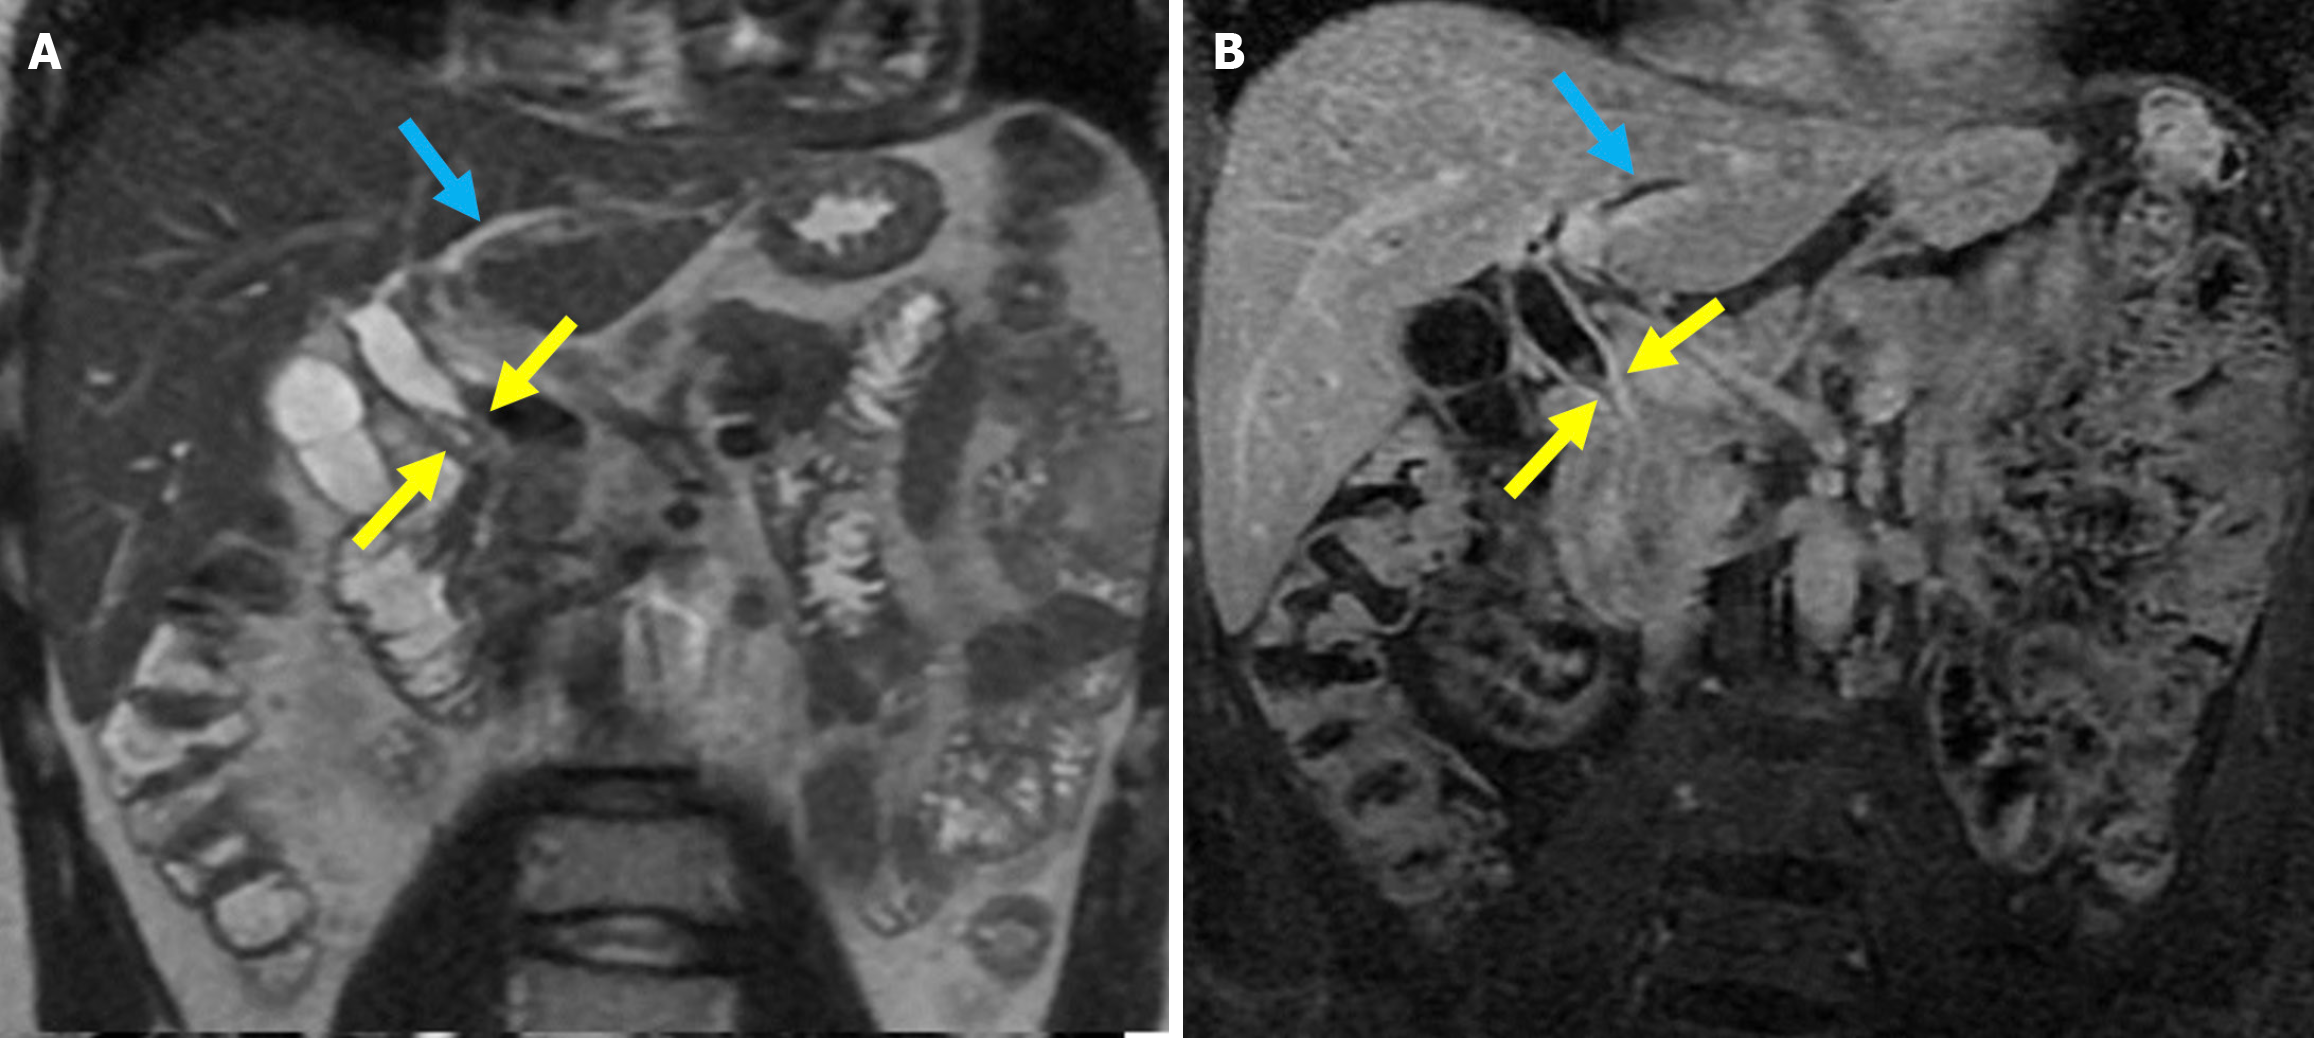

The revised Atlanta classification recognizes two primary forms of acute pancreatitis: NP and interstitial edematous pancreatitis (IEP). NP tends to follow a more severe clinical course with higher rates of infection, organ failure, and mortality. Imaging reveals hypoperfused or non-enhancing areas indicating NP or peripancreatic necrosis. Early collections (within 4 weeks) are referred to as acute necrotic collections. Once encapsulated after 4 weeks, they are known as walled-off necrosis (Figure 3)[23]. IEP is characterized by a diffusely enlarged pancreas with homogeneous enhancement on CECT imaging without areas of necrosis and with peripancreatic fat stranding and fluid accumulation. Fluid collections observed within the first 4 weeks are termed acute peripancreatic fluid collections, while those persisting beyond 4 weeks are classified as pancreatic pseudocysts (Figures 4 and 5).

Figure 3 Necrotizing pancreatitis, acute necrotic collections, and walled-off necrosis. A and B: Contrast-enhanced axial computed tomography (CT); C: T2-weighted magnetic resonance imaging (MRI); D: Post-contrast fat-suppressed T1-weighted MRI. A 76-year-old male patient underwent endoscopic retrograde cholangiopancreatography due to choledocholithiasis. On the evening of the procedure, the patient developed acute abdominal pain that was unresponsive to analgesics. Laboratory tests revealed elevated levels of aspartate aminotransferase, alanine aminotransferase, and lipase. Within the following 24 hours, the patient’s condition deteriorated and developed into shock. Subsequently, the patient required vasopressor support and intubation. Contrast-enhanced CT (A and B) was performed due to the severe abdominal pain. The images showed a markedly enlarged pancreas with areas of non-enhancement consistent with necrotizing pancreatitis that was accompanied by peripancreatic edema (yellow arrows). Heterogeneous acute necrotic collections were also observed in the peripancreatic region (blue arrows). Two months later, an MRI was performed for follow-up. On T2-weighted images (C) a collection with a heterogeneous internal structure and defined wall that was consistent with walled-off necrosis was visualized (orange double-sided arrow). There was a significant loss of pancreatic volume due to necrosis. In the post-contrast T1-weighted fat-suppressed image (D), contrast enhancement of the wall of the collection was noted. A small remnant of pancreatic tissue with normal contrast enhancement was observed (purple arrow).

MRI with its superior soft tissue resolution offers greater accuracy for the assessment of small necrotic regions of the pancreas[33]. Although MRI is less accessible and more costly than CT, it can be used for the diagnosis and follow-up of PEP. In IEP, pancreatic enhancement is preserved, and T2-weighted images typically reveal increased signal intensity, indicating pancreatic edema and peripancreatic inflammatory changes including fat stranding and fluid collections. In NP, decreased or heterogeneous enhancement areas are seen (Figure 3)[33]. In 20% of patients with NP, necrosis is confined to the peripancreatic fat without involvement of the pancreatic parenchyma. Patients in this category usually experience a more favorable disease course compared with those with glandular necrosis but a worse outcome than in individuals with IEP[34]. MRI is superior to CT in evaluating peripancreatic fat necrosis due to its enhanced soft tissue contrast[35]. MRI and MRCP are particularly valuable in visualizing the communication between pancreatic ducts and fluid collections. They aid in the diagnosis of disconnected pancreatic duct syndrome and determining the need for surgical intervention[33,35,36].

Walled-off necrosis typically appears as a partially liquefied collection containing solid necrotic tissue and fatty debris. The advantage of MRI in soft tissue contrast over CT enhances the accuracy in assessing the solid parts of pancreatic and peripancreatic collections. As the amount of solid debris increases, the effectiveness of drainage through stents or catheters tends to decrease. Therefore, MRI is particularly useful in guiding therapeutic decisions, including the need for endoscopic necrosectomy[36].